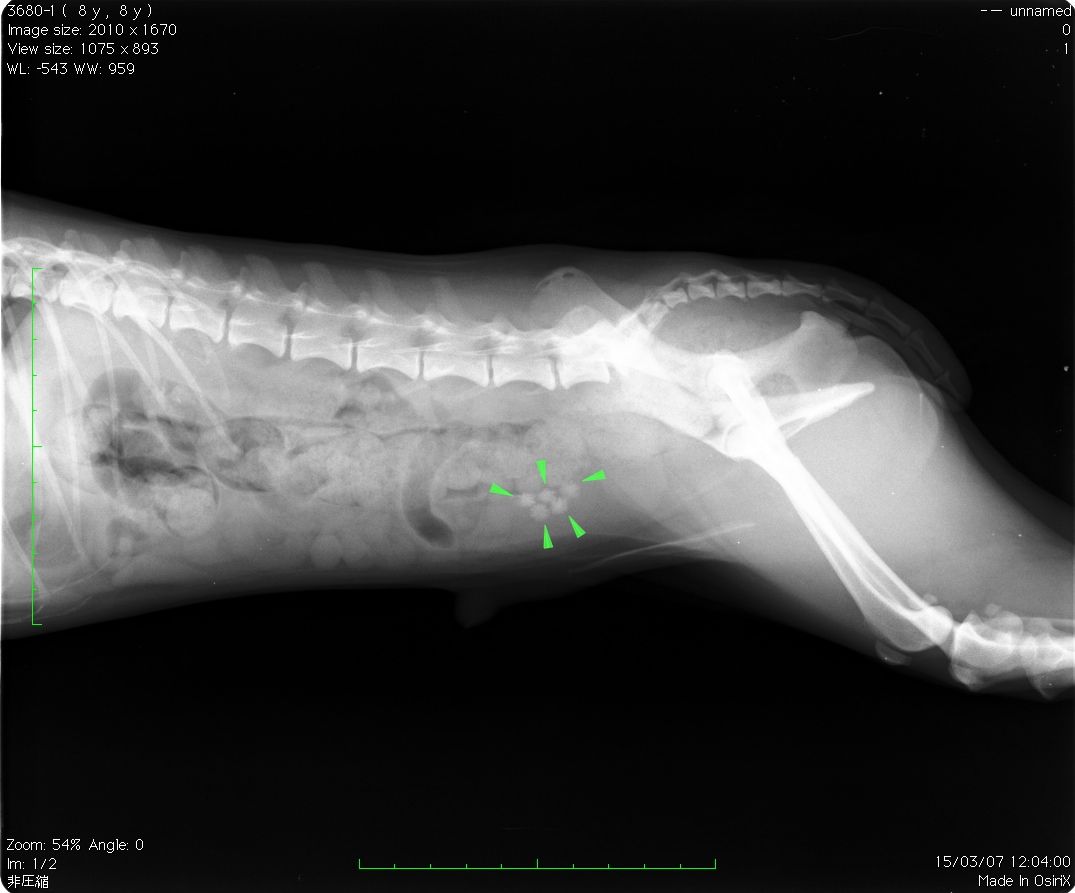

膀胱結石とは膀胱炎や食生活、飲料水の摂取減少や体質などにより尿中のカルシウムや マグネシウム、リンなどのミネラル成分が結合して結石を形成する病気です。 結石が作られた場所により時には腎不全や排尿痛を出す事もありますが、膀胱内結石では、 頻尿や血尿、難治性の膀胱炎や尿道炎が見られる事が多いとされます。 食餌や薬、サプリメント・漢方などにより溶解を試みたり、カテーテルを使用して 取り出したりもしますが、一定の大きさ以上で溶けない場合、 どうしても膀胱切開による摘出となります。 本日の症例はレントゲンで8mm大の結石が5つも見つかりましたので(以下)摘出しました。(以下)